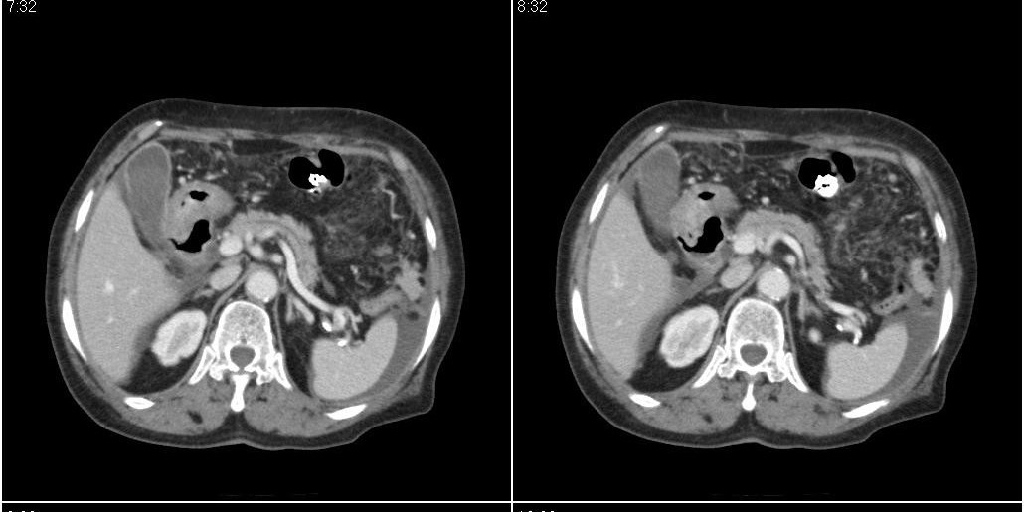

支持!另腹腔少量积液。

胆囊炎,胆结石,胆囊窝积液,胸腹水。

胆囊内稍高密度影,无强化,胆囊壁增厚,周围见低密度影,右侧膈肌角及脾周水样密度,支持胆囊泥沙样结石,胆囊炎、胆囊窝积液,胸腹水。